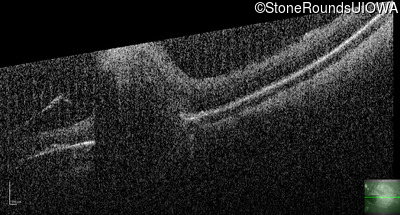

Optical Coherence Tomography - Right - 10/200

Exemplar / OCT Stack